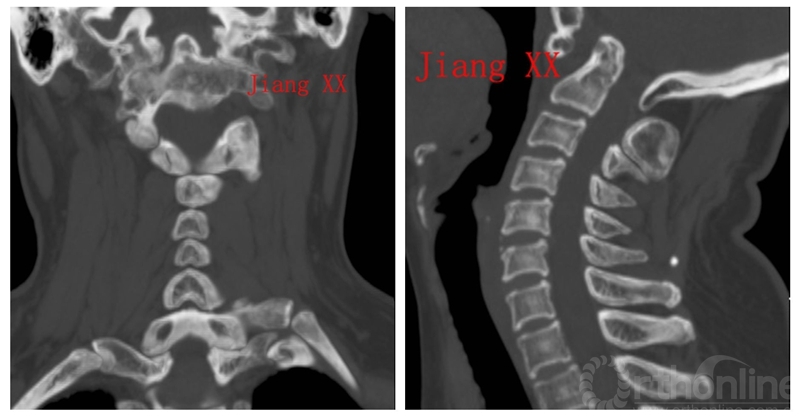

术前CT